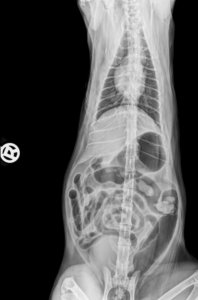

Hier Die Röntgenbilder das schwarze das zu sehen ist- ist das Augegaste.

53508ECC-0DD1-43B2-96DC-80E0F4C897AF.jpeg38B1B5B7-ACAB-402B-8249-9D48217B2176.jpeg

Emily war ganz aufgegast sie hatten Ultraschall gemacht Röntgenbilder hatte der Tierarzt Notdienst bei dem ich war der TK weitergeleitet.

Nach Medikamentengabe ist die Aufgasung zurückgegangen sodass man einen Fremdkörper ausschliessen kann.

Das Gas war aber noch im Verdauungstrakt, sodass man nicht alles mit dem Ultraschall sehen konnte.